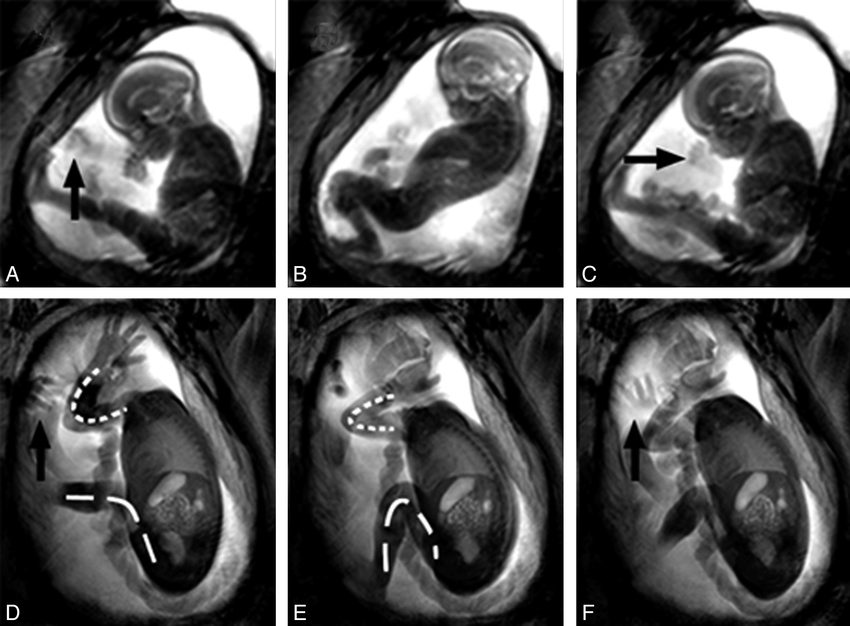

11. Otot tubuh

Di minggu ke-12 atau empat bulan kehamilan, fetus mulai bergerak-gerak di dalam perut ibunya. Ini karena otot mulai berkembang dan tersambung dengan sistem saraf. Itulah kenapa pada umumnya ibu baru akan merasakan tendangan dari si buah hati setelah empat bulan.

12. Organ dalam

Sebenarnya organ dalam sudah mulai berkembang setelah lima hingga enam minggu kehamilan. Mula-mula mereka tumbuh di luar tubuh, tetapi masih dilindungi oleh jaringan di atasnya. Usus, hati, lambung mulai muncul di usia tersebut. Hingga pada akhirnya, di minggu ke-14, organ tersebut akan tertata di sekitar dada dan perut.